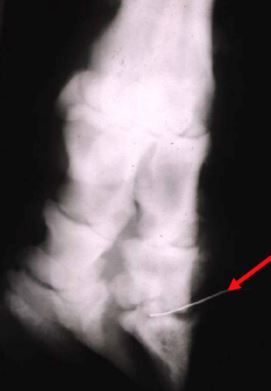

What’s your diagnosis if this malleable probe

is placed into the draining tract and

it falls right into the joint space?

A

Septic DIJ